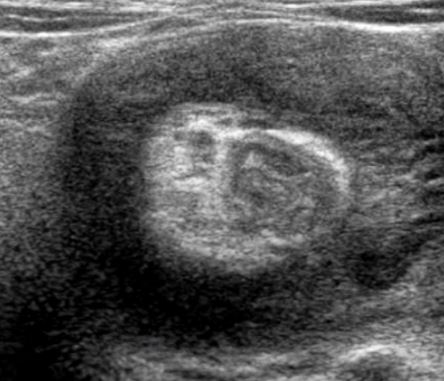

장중첩증 환자의 복부 초음파 사진. 장이 말려 들어가 겹쳐진 모양의 단면이 마치 도넛 모양으로 보인다.

진단을 위해 가장 먼저 복부 X-레이를 촬영한다. 이를 통해 장관 내의 가스 분포를 확인하거나, 만져지는 종괴의 음영을 확인하여 장중첩증을 의심할 수 있다. 이후 복부 초음파로 ‘도넛 사인’과 같은 특징적인 소견을 통해 정확한 진단을 할 수 있다. 장이 말려 들어가 겹쳐진 모양의 단면은 도넛 형태와 유사하다.